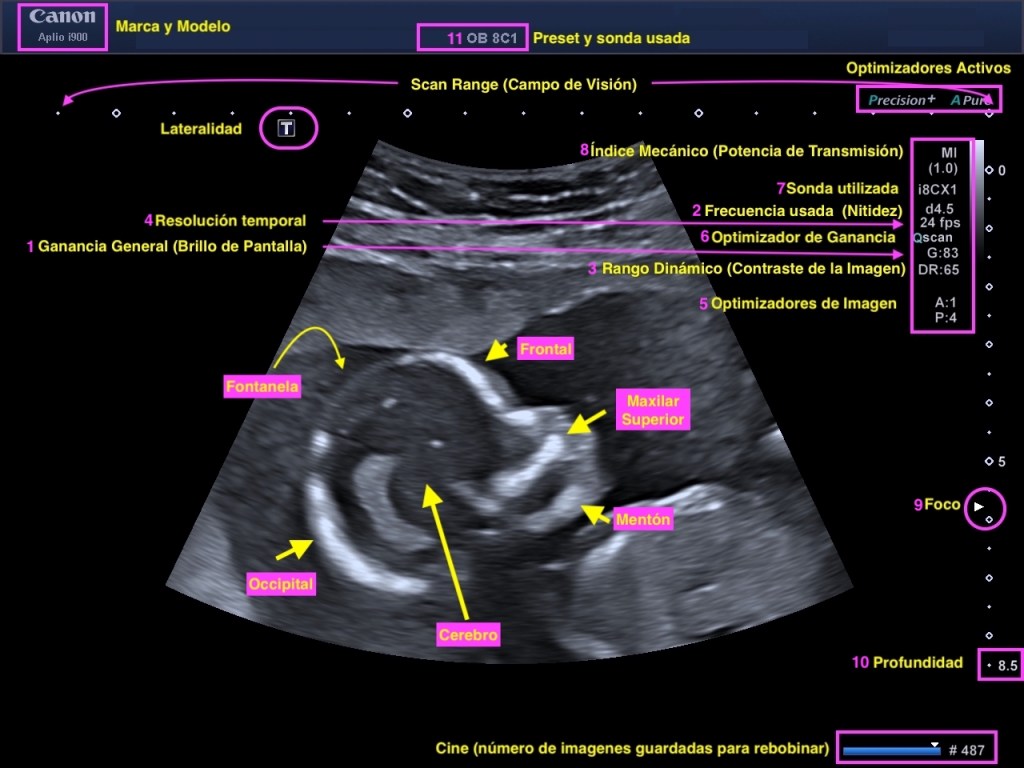

- Presentación sobre el valor del índice mecánico en la la ecografía y su relevancia en diagnóstico médico.

- Introducción a parámetros que afectan la seguridad del paciente y calidad de una ecografía.

- Definición: Medida que indica las vibraciones mecánicas generadas en tejidos durante la ecografía.

- Cálculo del MI: MI = Pico de presión negativa del ultrasonido / Raíz cuadrada de la frecuencia del ultrasonido.

- el Índice Mecánico (MI) es uno de los índices que se utiliza para evaluar la seguridad del ultrasonido en el cuerpo humano. El MI es particularmente importante porque se relaciona con el potencial de efectos no térmicos, como la cavitación.

- En términos de rangos de seguridad, el MI debería mantenerse lo más bajo posible para minimizar el riesgo de cavitación, especialmente en exámenes de diagnóstico. La mayoría de las directrices internacionales, como las de la FDA (Food and Drug Administration) en los Estados Unidos, recomiendan un MI máximo de 1.9 para la mayoría de los exámenes diagnósticos.